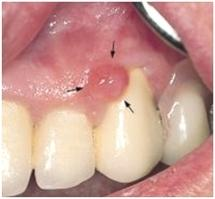

Aspect typique d’un aphte

Les épulis

Ce sont des excroissances bénignes de la gencive, qui saignent facilement et qui peuvent avoir des causes multiples. Leur traitement consiste en leur exérèse.

Aspect d’une épulis